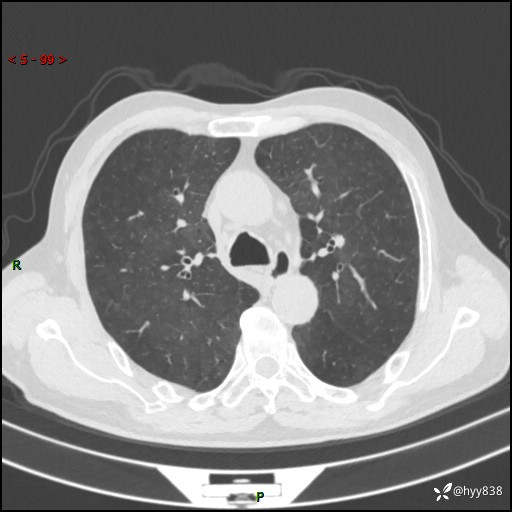

辅助检查:CT

胸部CT平扫